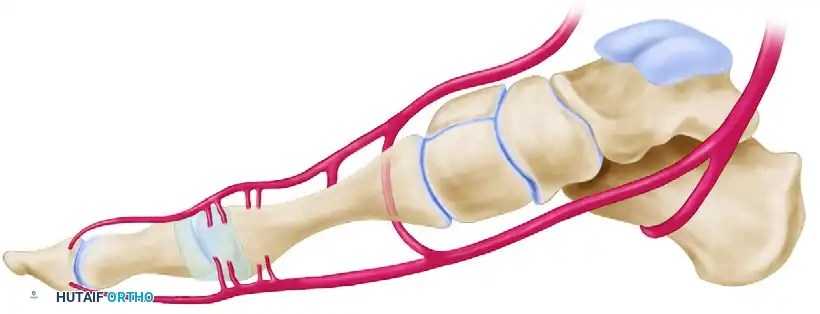

The vascular supply to the first metatarsal head is delicate and highly susceptible to iatrogenic injury during corrective osteotomies and capsular releases. A thorough comprehension of the extraosseous and intraosseous arterial networks is mandatory for any reconstructive foot and ankle surgeon.

The Medial and Plantar Blood Supply

The primary blood supply to the first metatarsal head is derived from the first dorsal metatarsal artery, the first plantar metatarsal artery, and the superficial branch of the medial plantar artery. These vessels give rise to a rich network of pericapsular perforators that enter the metatarsal head distally. The principal nutrient artery enters the lateral aspect of the metatarsal shaft proximally.

Surgical Warning: The site of a cortical osteotomy must remain strictly within the interval between the pericapsular perforators distally and the nutrient artery proximally. Violation of this safe zone significantly increases the risk of osteonecrosis.

The Dorsal Vulnerability

From a dorsal perspective, the relationship between the osteotomy site, the nutrient artery, and the distal pericapsular perforators becomes highly apparent. The first dorsal metatarsal artery and its branching network are especially vulnerable to overpenetration of the lateral cortex by an oscillating saw during the osteotomy cut.

Safe Zones for Lateral Capsular Release

When a lateral capsular release is indicated to correct residual deformity, it must be executed with precision. The safe zone for a lateral capsular release spares all perforators entering the metatarsal head proximally and all perforators entering the proximal phalanx distally. This is achieved as long as the capsulotomy is performed strictly in line with the metatarsophalangeal (MTP) joint in the coronal plane.